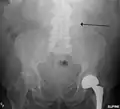

An abdominal aortic aneurysm is usually diagnosed by physical exam, abdominal ultrasound, or CT scan. Plain abdominal radiographs may show the outline of an aneurysm when its walls are calcified. However, the outline will be visible by X-ray in less than half of all aneurysms. Ultrasonography is used to screen for aneurysms and to determine their size if present. Additionally, free peritoneal fluid can be detected. It is non-invasive and sensitive, but the presence of bowel gas or obesity may limit its usefulness.[30] CT scan has nearly 100% sensitivity for an aneurysm and is also useful in preoperative planning, detailing the anatomy and possibility for endovascular repair. In the case of suspected rupture, it can also reliably detect retroperitoneal fluid. Alternative less often used methods for visualization of an aneurysm include MRI and angiography.[31]

Abdominal aortic aneurysms are commonly divided according to their size and symptomatology. An aneurysm is usually defined as an outer aortic diameter over 3 cm (normal diameter of the aorta is around 2 cm),[43] or more than 50% of normal diameter.[44] If the outer diameter exceeds 5.5 cm, the aneurysm is considered to be large.[42] Ruptured AAA should be suspected in any person older than 60 who experiences collapse, unexplained low blood pressure, or sudden-onset back or abdominal pain. Abdominal pain, shock, and a pulsatile mass are only present in a minority of cases. Although an unstable person with a known aneurysm may undergo surgery without further imaging, the diagnosis will usually be confirmed using CT or ultrasound scanning.